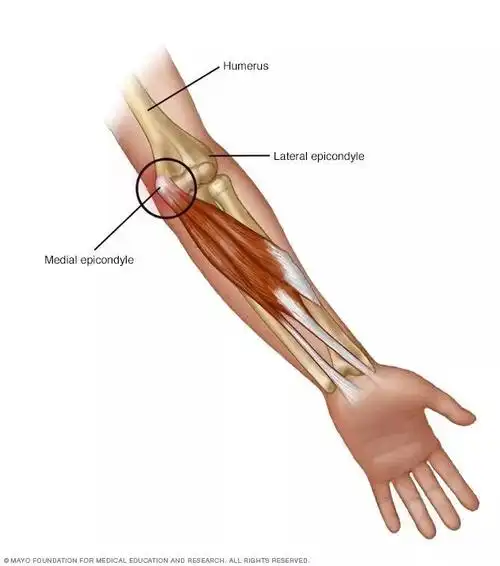

手肘疼胀怎么办?高尔夫球肘?

疼痛科网球肘――肘关节疼怎么办?